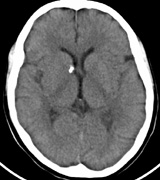

1. Superficial cortical sclerosis (parenchymal hamartoma) which distort the gyri. Microscopy shows large atypical fibrillary type astrocytes with few associated neurons and areas of calcification.133 The numerous abnormal glial processes and fibers make the tissue abnormally firm or “sclerotic” on palpation (Fig. 13).132

2. Subependymal nodules (SEN) are typically found along the lateral borders of the ventricles and parehncymal brain lesion (“cortical tubers”) (Figs. 14 and 15). Calcification in the first year of life is rare.132

On MRI imaging, the subependymal nodules and parenchymal brain lesions of infants (age ≤3 months) and adults show different signal characteristics. Infant CNS tubers are hyperintense on T1-weighted images and hypointense on T2-weighted images, which is the opposite of the pattern seen in adults.134 Malignant transformation of SEN occurs in about 10% to 15% of patients and the resultant subependymal giant cell astrocytoma accounts for 25% of premature deaths in TSC.135,136

Fig. 15. Tuberous Sclerosis Complex. (a) Patient 1: Axial CT scans demonstrating typical calcification of subependymal nodules in a 13-year-old girl with a history of seizures. (b and c) Patient 2. (b) Axial T2-weighted images demonstrate calcified subependymal nodules (arrowheads) and cortical tubers typical of tuberous sclerosis. (c) Widespread cortical tubers are seen on a coronal FLAIR sequence as thickening of the cortex and high signal of the subcortical white matter.